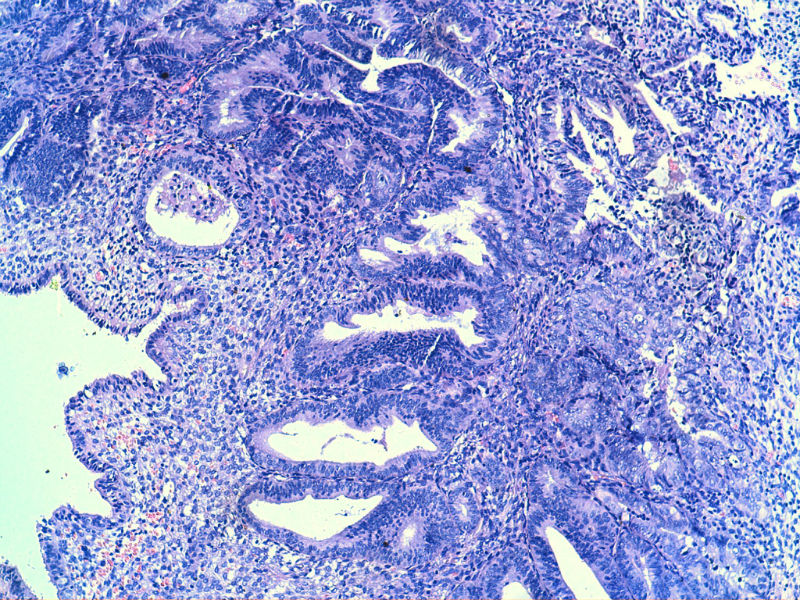

子宫内膜EIN?

子宫内膜EIN?图1

名称:图1

描述:image_2000y01m01d_08h08m34s

图13是做为正常对照的,图7、8、9、12显示的核大小不一,空泡状,形状不规则。女,48岁,宫血半年